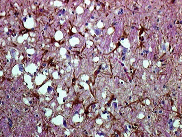

"BSE (see glossary) is a chronic, degenerative disease affecting the nervous system of cattle" (Pratt). The disease causes loss of muscular coordination, nervousness, and severe muscular twitching (Fact Sheet). Infected cattle tend to stand away from the herd and lose weight, although no loss of appetite occurs. The disease gets its name "spongiform" because it literally bores microscopic holes in the brain, making the brain appear spongy (see Fig. 2&3). Once clinical signs appear, the disease is always fatal. Although a fairly recent disease, over 150,000 cows have been diagnosed.

Figure 2. Sheep brain with scrapie. Magnification 250x (Typical).

Figure 3. Sheep brain with scrapie. Magnification 500x ( Typical).

History of CJD

Creutzfeldt-Jakob disease occurs worldwide. This disease, like Bovine Spongiform Encephalopathy, bores actual holes into the brain (see Fig. 4). It appears sporadically, striking one person in a million (Prusiner). The disease is so contagious that a majority of neurologists refuse to do autopsies on these patients, making the estimated "1 in a million" possibly severly underestimated. The incubation period is very long in humans. An innocent child could be slowly dying of this disease and not know it until their late thirties. Clinical symptoms start with changes in sleeping and eating and deteriorate over a few weeks. People with CJD will "wake up one morning twitching and deteriorate weekly into blindness and epilepsy while their brain perforates into a sponge" (Greger).

Figure 4. Human Brain with CJD (Creutzfeldt).